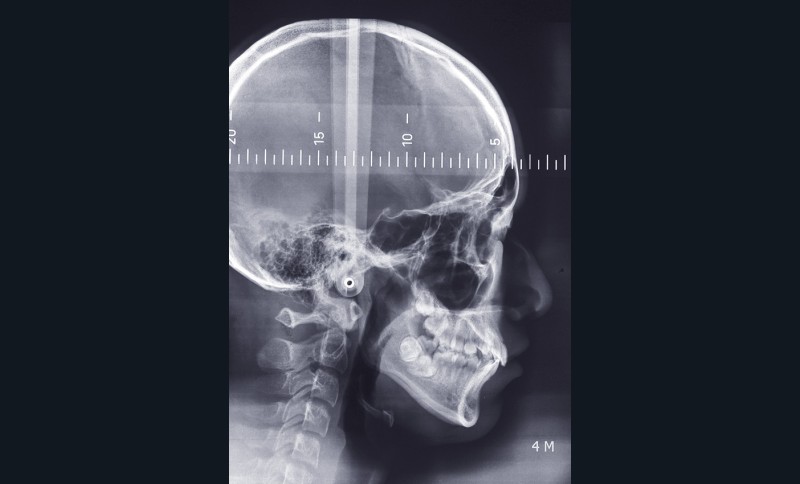

Sur le plan squelettique, le patient présente une classe I de Ballard sur un schéma hyperdivergent et une rotation postérieure de Björk. Le patient se situe au stade Cvs 4 de maturation des vertèbres cervicales, soit en plein dans son pic de croissance (fig. 10).